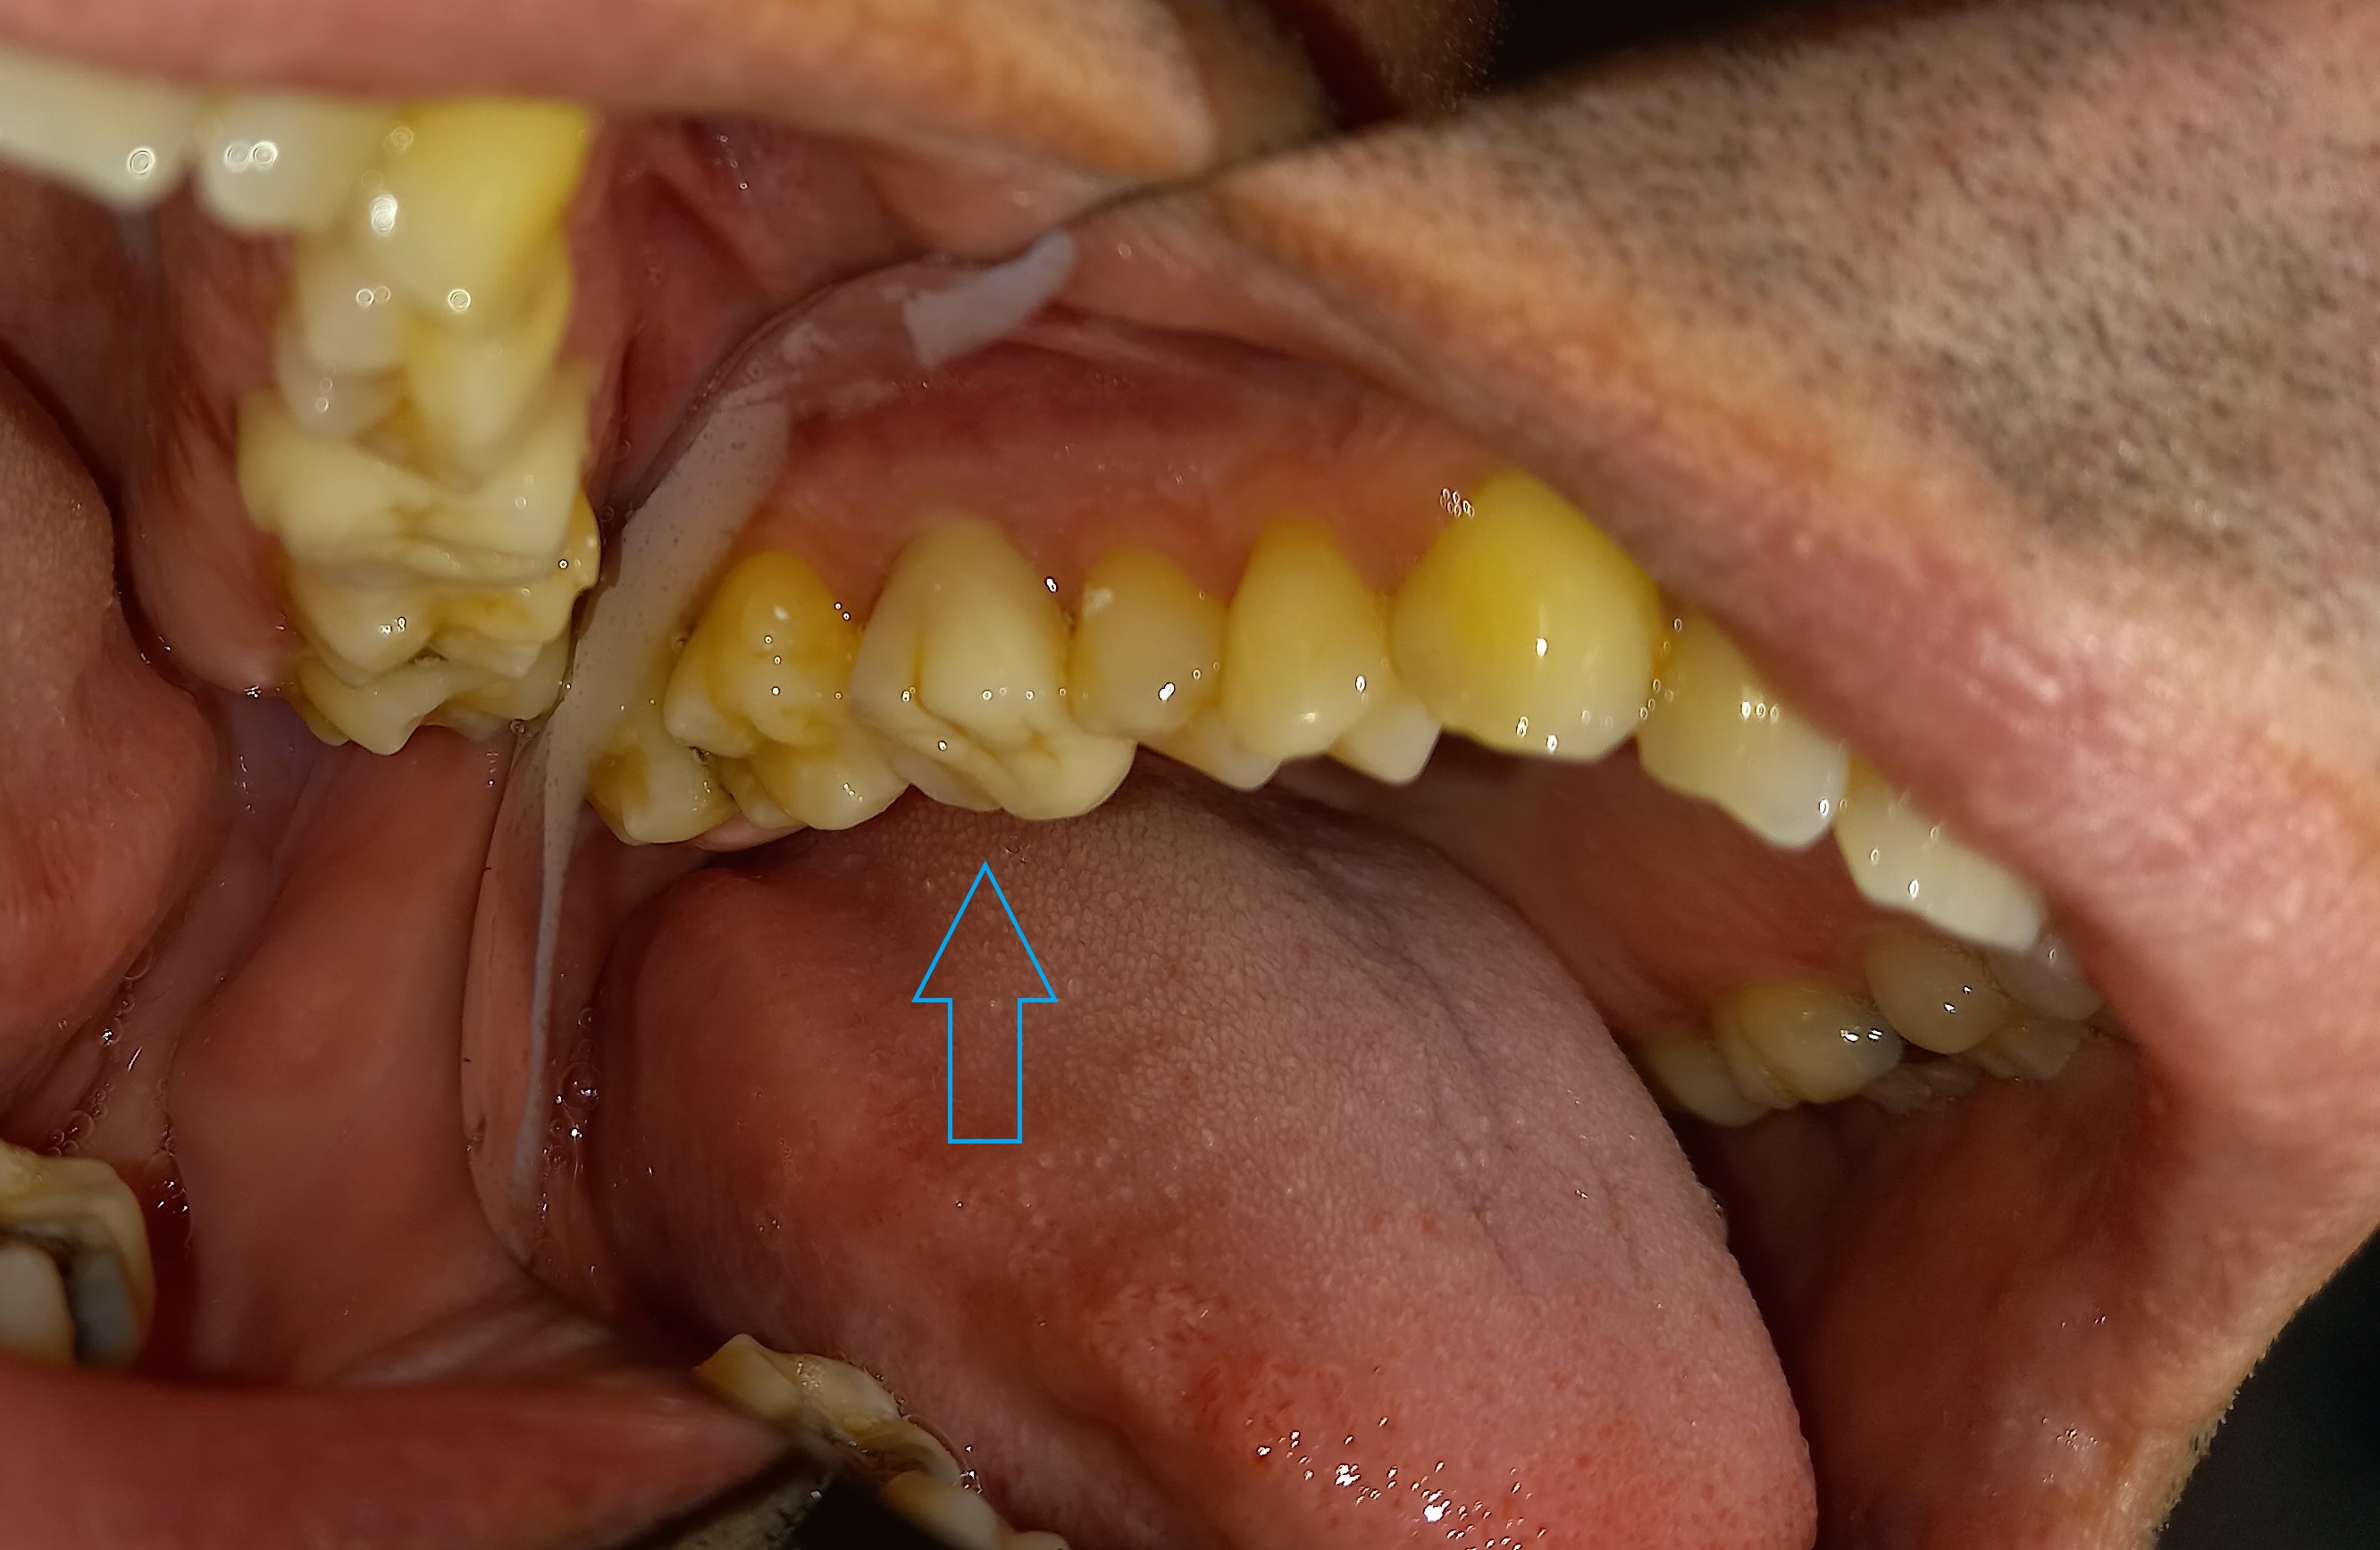

Αρχική κλινική εικόνα του μεγάλου οδοντικού ελλείμματος